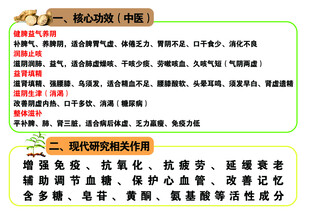

黄精 共享分:40

黄精 共享分:40 -

黄精的功效 共享分:40

黄精的功效 共享分:40 -